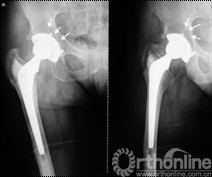

女,50岁,因髋关节发育不良继发骨关节炎行混合性固定(非骨水泥髋臼,骨水泥柄)THA手术。术后6年4个月发现腹股沟部渐增大、无痛性包块;体查:关节活动正常,腹股沟处可触及一10mm×10mm大小、质中等、移动度差、无触痛包块。超声检查提示右髂窝包块,呈强弱不等回声,大小约12cm×10cm,边界清楚。Harris评分88分。X线片示髋臼顶部DeLee和Charnley II区不规则低密度透光区,无连续骨小梁(图5)。CT片示髋臼假体上方DeLee和Charnley II区骨溶解区,DeLee和Charnley I、III区髋臼假体骨长入固定(图6)。WBC6.7×109/L,中性64%,ESR 28mm/h,CRP 8.34mg/L。聚乙烯线性磨损率为0.17mm/年,容积磨损率为543.42mm3/年,骨溶解区面积为412.52mm2。诊断:THA术后髋臼假体周围局灶性骨溶解(假体稳定)伴假性瘤样形成。

图5 翻修术前髋关节正侧位X线片示髋臼顶部DeLee和Charnley II区不规则低密度透光区(箭头所示),髋臼假体稳定固定

图9 髂腹股沟入路炎性假瘤切除、骨溶解病灶清除、同种异体颗粒骨植骨,髋关节后外侧入路更换高分子聚乙烯内衬为高交联聚乙烯内衬、更换股骨头术后

图10 术后2年随访,植骨替代吸收,髋臼骨溶解区新生骨组织替代,髋臼假体无移位、假体稳定固定